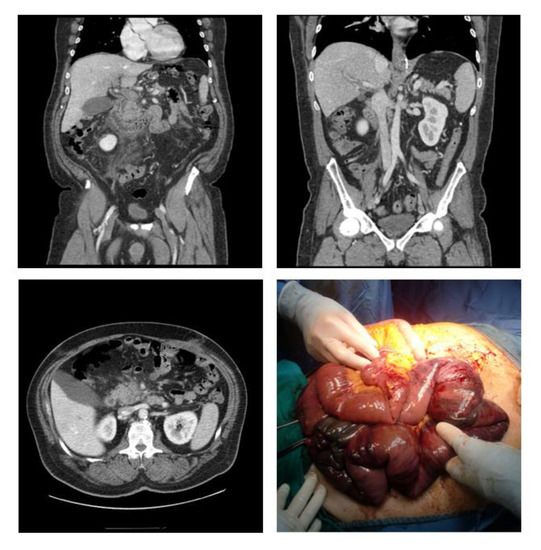

Superior Mesenteric Vein Thrombosis Icd. When you have mesenteric venous thrombosis MVT you have a blood clot in a vein around where your intestines attach to your belly. Intraoperative assessment of bowel viability is mandatory and evaluation of the patency of the superior mesenteric vein SMV is necessary. Mesenteric artery vein embolism. Mesenteric artery vein embolism.

It can affect the ileum 6483. In line with ICD-10-CM Pointers an preliminary encounter. Despite its severe consequences SMVT often presents with nonspecific symptoms such as nausea vomiting and abdominal pain. Index to Diseases and Injuries. S3533 Injury of superior mesenteric vein. ICD Code S3533 is a non-billable code.

Index to Diseases and Injuries. Superior mesenteric vein complete transection. Superior mesenteric vein thrombosis SMVT is a rare yet frequently fatal cause of intestinal ischemia. The Index to Diseases and Injuries is an alphabetical listing of medical terms with each term mapped to one or more ICD-10 codes. This case report in contrast involves superior mesenteric and left portal vein septic thrombosis in a backpacker following prolonged hiking and abdominal straining.

Superior mesenteric vein thrombosis icd 10. Superior mesenteric vein laceration ICD-10-CM Diagnosis Code S35331A Laceration of superior mesenteric vein initial encounter. The patient was diagnosed with acute ischemia of the ascending colon due to mesenteric vein thrombosis which was attributed to Antithrombin III deficiency. Mesenteric artery vein thrombosis. S3533 Injury of superior mesenteric vein.

Superior mesenteric vein thrombosis SMVT is a rare yet frequently fatal cause of intestinal ischemia. BILLABLE CODE - Use S35331A for initial encounter. Index to Diseases and Injuries. ICD-10 from 2011 - 2016. Superior mesenteric vein thrombosis SMVT is a rare yet frequently fatal cause of intestinal ischemia.

The superior mesenteric vein in 95 of cases and the inferior mesenteric vein which supplies the well-collateralized distal colon in only 4 to 6 of cases1 Acute MVT is typically caused by new-onset symptomatic thrombo-sis of the superior mesenteric vein or its branches without collateralization. If the SMV is occluded thrombectomy should be performed and local thrombolysis can be undertaken via a transmesenterically inserted catheter fig. S3533 Injury of superior mesenteric vein. Consider using any of the following ICD-10 codes with a higher level of specificity when coding for laceration of superior mesenteric vein. Superior Mesenteric Artery Syndrome SMAS Thromboembolus not Cerebral Total Hip Replacement THR.